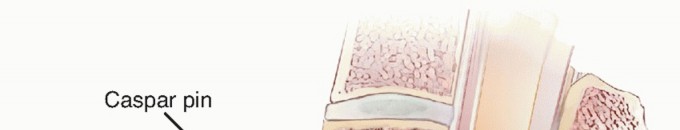

### FIG 1 • Anterior foraminotomy anatomy: important anatomic relationships to consider when performing anterior cervical spine surgery. The exiting nerve root enters the foramen at a 45-degree ventrolateral angle. The posterior aspect of the uncinate joint marks the entry zone of the neuroforamen, and it is where osteophytes commonly arise to impinge the exiting root. Thus, the uncus should be decompressed when performing foraminotomy. It is critical to hug the posterior aspect of the uncinate during foraminotomy to avoid injuring the exiting root, which lies immediately dorsal. The vertebral artery is less likely to be injured while working in the posterior disc space (eg, during decompression) because it is located at roughly the level of the middle third of the vertebra. The trajectory of discectomy should be bounded by the uncinates at all times, but it can widen posteriorly at the level of the nerve root to thoroughly decompress the root while avoiding vertebral artery injury (dashed blue line). The PLL (dashed yellow line) tends to be thicker and better defined centrally; it thins out laterally. The posterior longitudinal ligament (PLL) is a smooth and shiny group of dense ligaments that course along the posterior surface of the vertebral bodies within the spinal canal. The PLL tends to be thicker centrally and thins out laterally as it attaches to the uncinate regions. Bulging or ossification of the PLL (OPLL) can cause spinal cord compression. The intervertebral disc comprises the outer annulus fibrosus and the central gelatinous nucleus pulposus. Each disc is attached to the subchondral bone of the adjacent vertebral bodies. The outermost rim of the vertebral endplate is not attached to the disc, leaving a ring of exposed bone that may be more prone to forming arthritic spurs. The uncovertebral joints are critical bony landmarks for anterior cervical decompression (FIG 1). Spurs commonly arise from these articulations and cause impingement of the exiting roots as they enter the foramen. Depending on the cervical level, the vertebral artery may be as close as 5 mm away from the medial aspect of the uncinate process. ##

Each cervical spinal nerve is composed of dorsal and ventral roots. The ventral root lies dorsal to the uncovertebral joint, whereas the dorsal root is ventral to the superior articular facet. It is important to keep in mind when performing uncovertebral osteophyte resection that the nerve root leaves the spinal cord at roughly a 45-degree angle ventrolaterally in the axial plane. Thus, care must be taken to hug the posterior surface of the uncinate to avoid injury to the exiting root.4 ## PATHOGENESIS Neural impingement occurs in two main locations: within the spinal canal, affecting the spinal cord, the nerve root, or both; or within the foramen, where the exiting root can be affected. Depending on whether the involved structure is the spinal cord or the nerve root, patients can present with symptoms of myelopathy, radiculopathy, or both. ## NATURAL HISTORY The natural history of cervical radiculopathy is generally favorable with most patients having spontaneous resolution or considerable improvement of their symptoms over time. It is not common for radiculopathic patients to progress to myelopathy.9,10 ## HISTORY AND PHYSICAL FINDINGS Patients with radiculopathy typically present with radiating pain, paresthesia, or motor weakness (Table 1). However, the pattern of symptoms is not always dermatomal (FIG 2). On examination, patients with radiculopathy may have motor, sensory, or reflex changes along the affected nerve root distribution. However, the neurologic examination findings may be normal. Patients may express exacerbation of radicular pain with particular head positions (ie, head positions that narrow the size of the neural foramen such as neck extension with rotation to the affected extremity). This can be elicited by performing the Spurling test. The Spurling sign is very helpful in differentiating cervical radiculopathy from extraspinal causes, such as cubital or carpal tunnel syndromes, as reproduction of symptoms should occur only with a cervical source of compression. ## IMAGING AND OTHER DIAGNOSTIC STUDIES Plain radiographs, although of limited value in evaluating neural compression, remain a commonly acquired initial study and can be used to evaluate overall alignment, spinal instability, or bony pathology, including spur formation. Magnetic resonance imaging (MRI) is the modality of choice for evaluating neural compression. Computed tomography (CT) myelography provides outstanding resolution of bony and neural anatomy, but it is less appealing as it requires an invasive procedure. It is typically recommended for patients with contraindications to MRI (eg, prosthetic heart valve, pacemaker) or when MRI fails to provide sufficient detail.